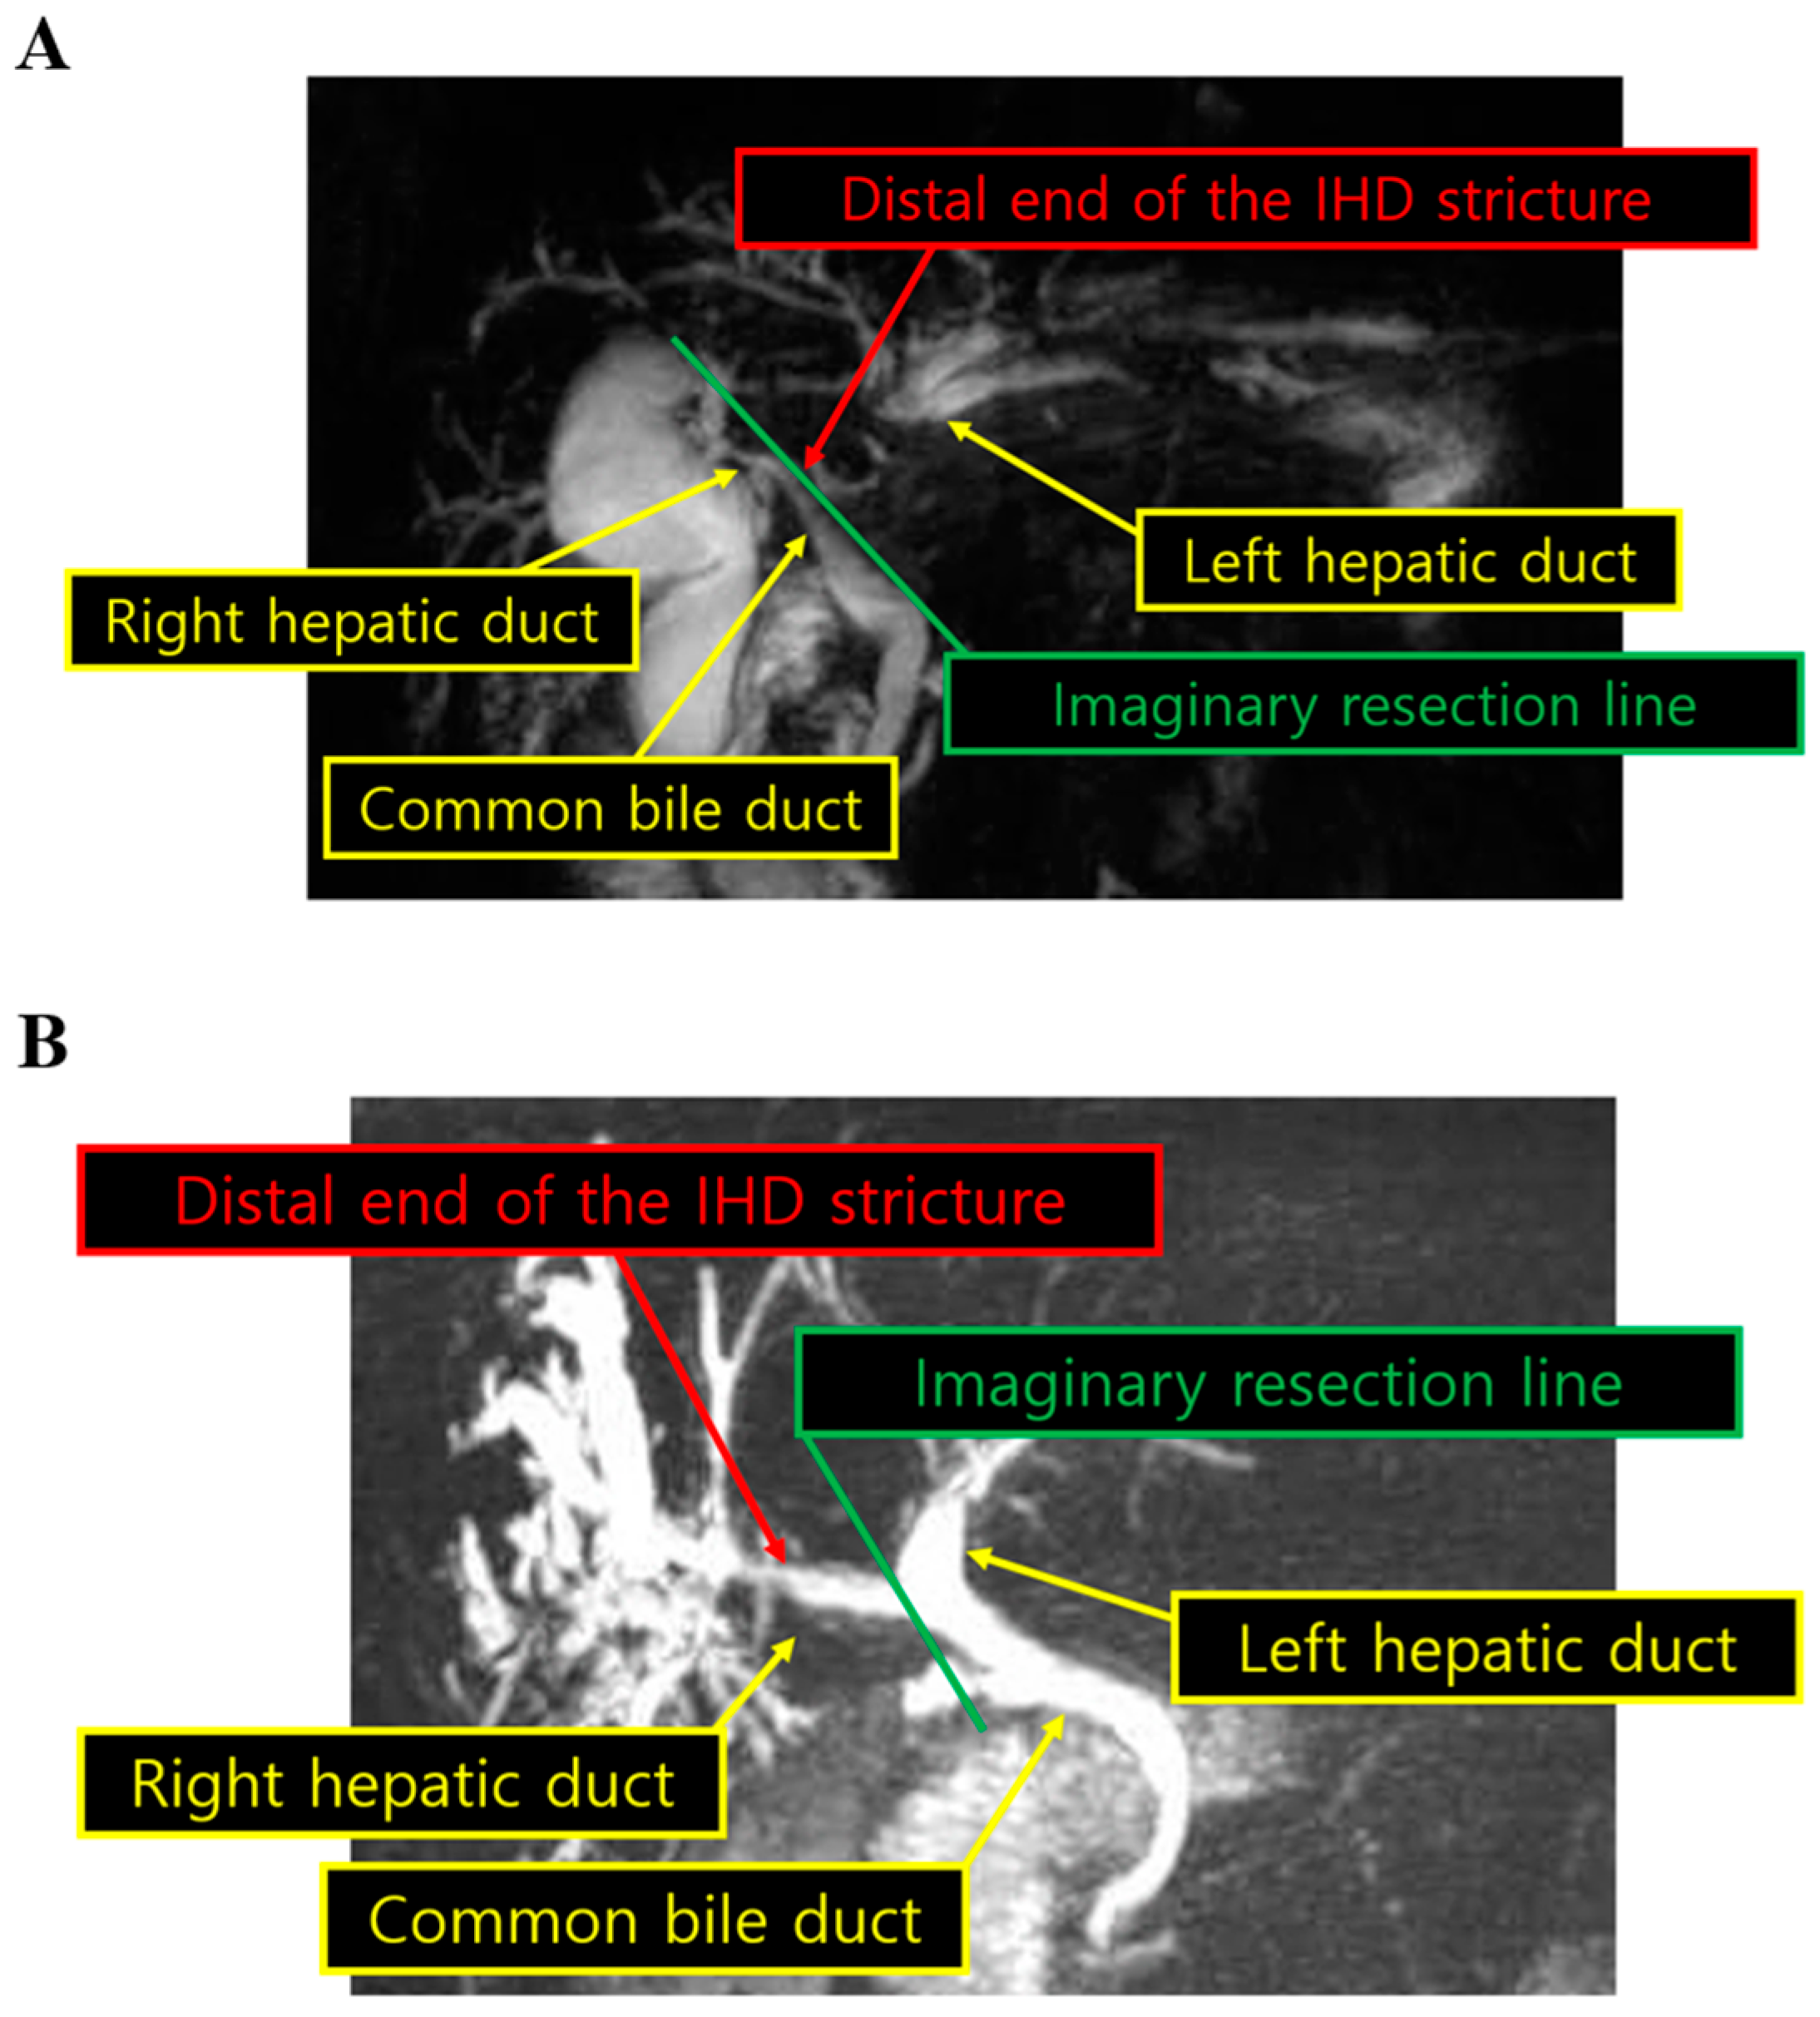

2.2. Surgical Techniques

| IHD stricture <1 mm from the bifurcation, n (%) | 63 (51.2%) |